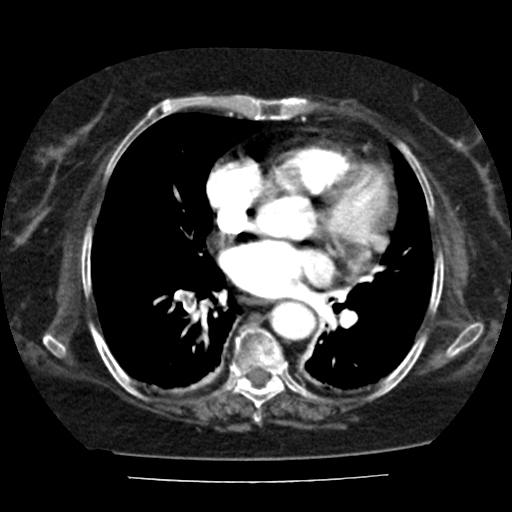

Presentamos el caso de una paciente femenina de 80 años que acudió a evaluación médica por disnea progresiva, fatiga y limitación funcional reciente, con sospecha clínica de tromboembolia pulmonar. Debido al deterioro respiratorio y factores de riesgo cardiovasculares asociados, se solicitó una angiotomografía de tórax para valoración vascular pulmonar.

El estudio demostró defectos de llenado intraluminal en arterias segmentarias medias e inferiores del pulmón derecho, compatibles con tromboembolia pulmonar aguda periférica. Asimismo, se documentó dilatación del tronco y de las arterias pulmonares principales, hallazgos sugestivos de hipertensión pulmonar.

Adicionalmente, se observó cardiomegalia significativa, con reflujo leve del medio de contraste hacia las venas suprahepáticas, hallazgo que sugiere compromiso hemodinámico compatible con cardiopatía congestiva. El parénquima pulmonar mostró patrón septal y en mosaico con áreas en vidrio deslustrado, en relación con congestión pulmonar leve. Se identificó también derrame pleural laminar bilateral asociado a atelectasias laminares.

Entre los hallazgos adicionales se encontraron signos de esteatosis hepática, probable litiasis vesicular, pequeña hernia hiatal por deslizamiento y cambios osteodegenerativos de la columna dorsal.